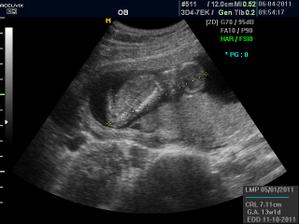

Pidižva č.2 a č.3... :o)